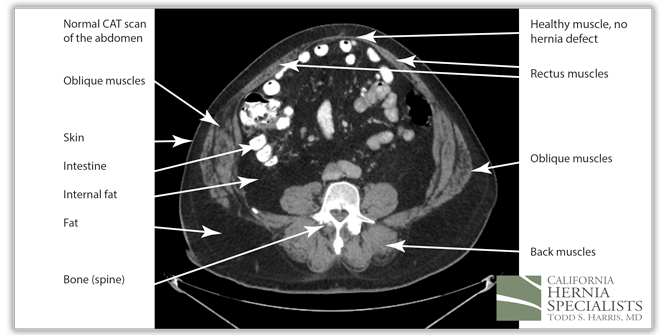

The CAT scan image above shows normal muscles of the abdominal wall with no evidence of a hole, or a hernia.

The 3 CAT scan images below show the patients normal muscles above the hernia, then a large hernia defect or hole in the muscle, and then the normal muscles again below the hernia defect.

The above image shows the upper part of this patients abdomen. No hernia is seen here; only normal muscles.